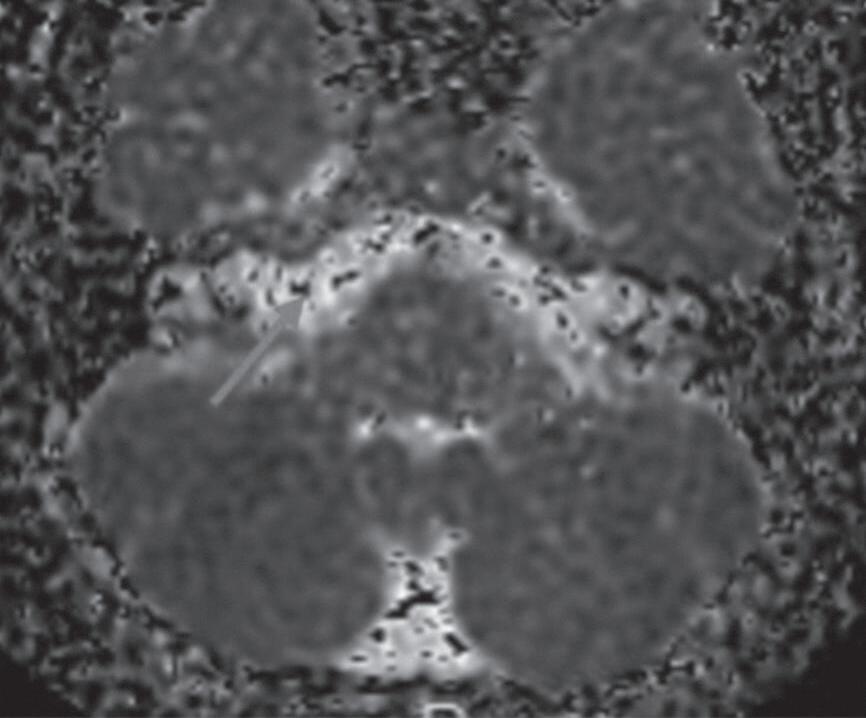

Difusão refere-se ao movimento randômico das moléculas de água no meio, conhecido como movimento browniano. O sinal hiperintenso na sequência difusão pode decorrer da restrição à difusão ou do aumento do tempo de relaxação T2 do tecido (efeito T2), questão que pode ser esclarecida com a medida do coeficiente de difusão aparente (ADC). De forma simplista, quando a lesão restringe a difusão, o ADC exibe hipossinal.

A sequência difusão pode ser utilizada na avaliação das orelhas para caracterizar colesteatomas, cistos epidermoides na cisterna do ângulo pontocerebelar, demonstrar coleções purulentas intra e extratemporais, principalmente intracranianas, investigar tumores da base do crânio intra e extra-axiais que apresentem relação núcleo/citoplasma alta (Figs. 1-19 e 1-20).

Fig. 1-19. Sequência difusão e mapa de ADC. RNM sequência difusão e mapa de ADC: não se observa área de restrição à difusão; liquor com sinal hiperintenso no mapa de ADC que indica difusão facilitada (seta vermelha).